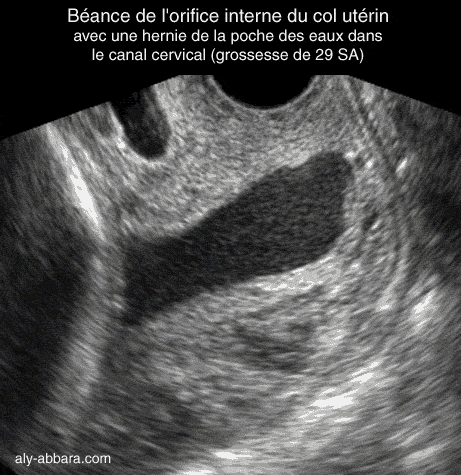

Coupe sagittale passant par le col utérin à 29 semaines d'aménorrhée

Il s'agit d'un col long de 51 mm avec orifice interne béant et une hernie de la poche des eaux

dans le canal endocervical.

A noter que le toucher vaginal (TV) ne permettait pas de diagnostiquer cette

incompétence

cervico-isthmique

, car lors de cet examen le col paraissait long de 3 cm et fermé